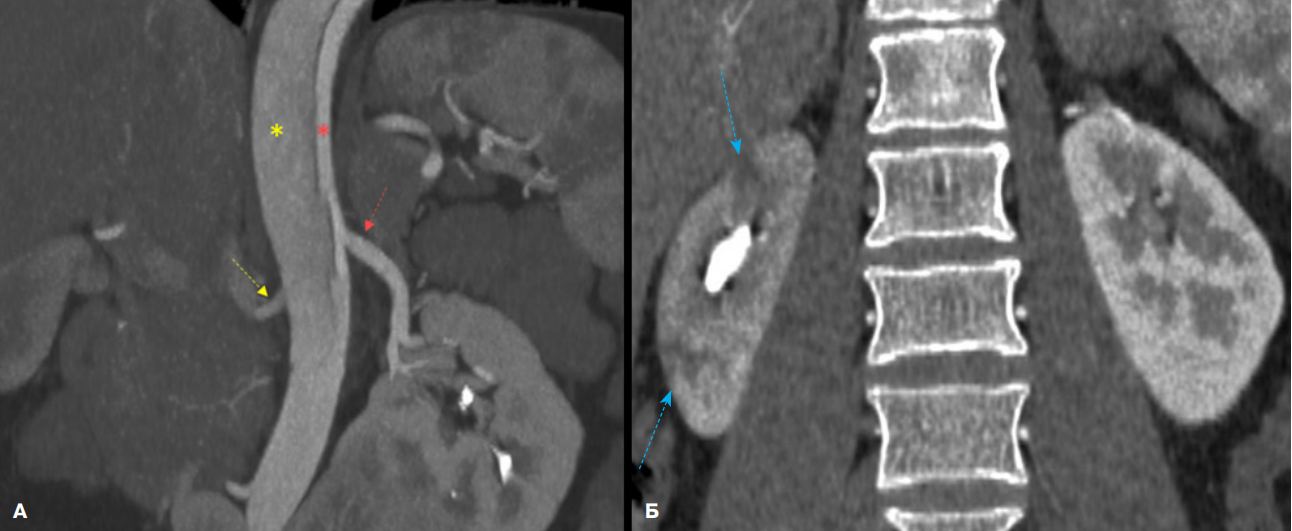

По решению врачебного консилиума для верификации диагноза выполнены КТ-панаортография и эхокардиография. Данные КТ-панаортографии подтвердили наличие расслоения, протянувшегося от уровня, расположенного дистальнее отхождения левой подключичной артерии, и до инфраренального сегмента брюшной аорты. Сопутствующей находкой явилась подковообразная почка с очагом инфаркта в паренхиме правой половины почки (рис. 1, 2).

Рис. 2. КТ-панаортография пациента с РА тип III (De Bakey).

Примечание: А — фронтальная плоскость (на уровне отхождения почечных артерий), Б — фронтальная плоскость (на уровне почек). Правая почечная артерия (желтая стрелка) отходит из ложного просвета, в отличии от левой почечной артерии (красная стрелка). Имеются различия общей перфузии паренхимы почек за счёт снижения контрастирования правой почки с формированием инфарктов (синие стрелки), а также слияние нижних полюсов почек (подковообразная почка). Цветное изображение доступно в электронной версии журнала.